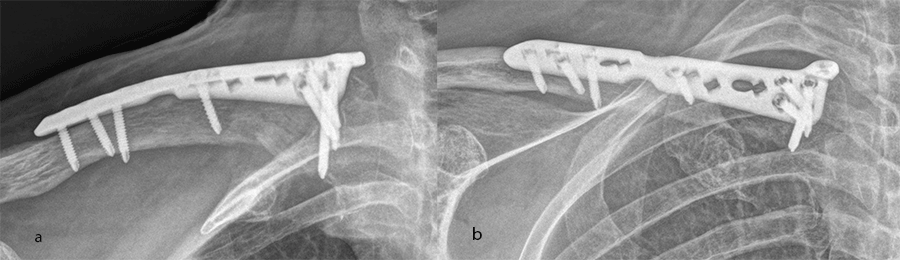

Case 2: shaft plate

A 54-year-old man sustained a mid-shaft fracture to his right clavicle following a 2 m fall from a ladder (Fig 13). Intraoperative images show plate placement and screw insertion (Fig 14). Postoperative image depicting minimal incision size for plate insertion before wound closure (Fig 15). Image shows the fracture healing at 6 weeks’ follow-up (Fig 16).